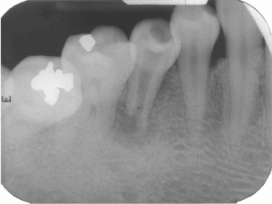

Figure 3

Periapical view: 6 years later.

Figure 3 Periapical view: 6 years later.